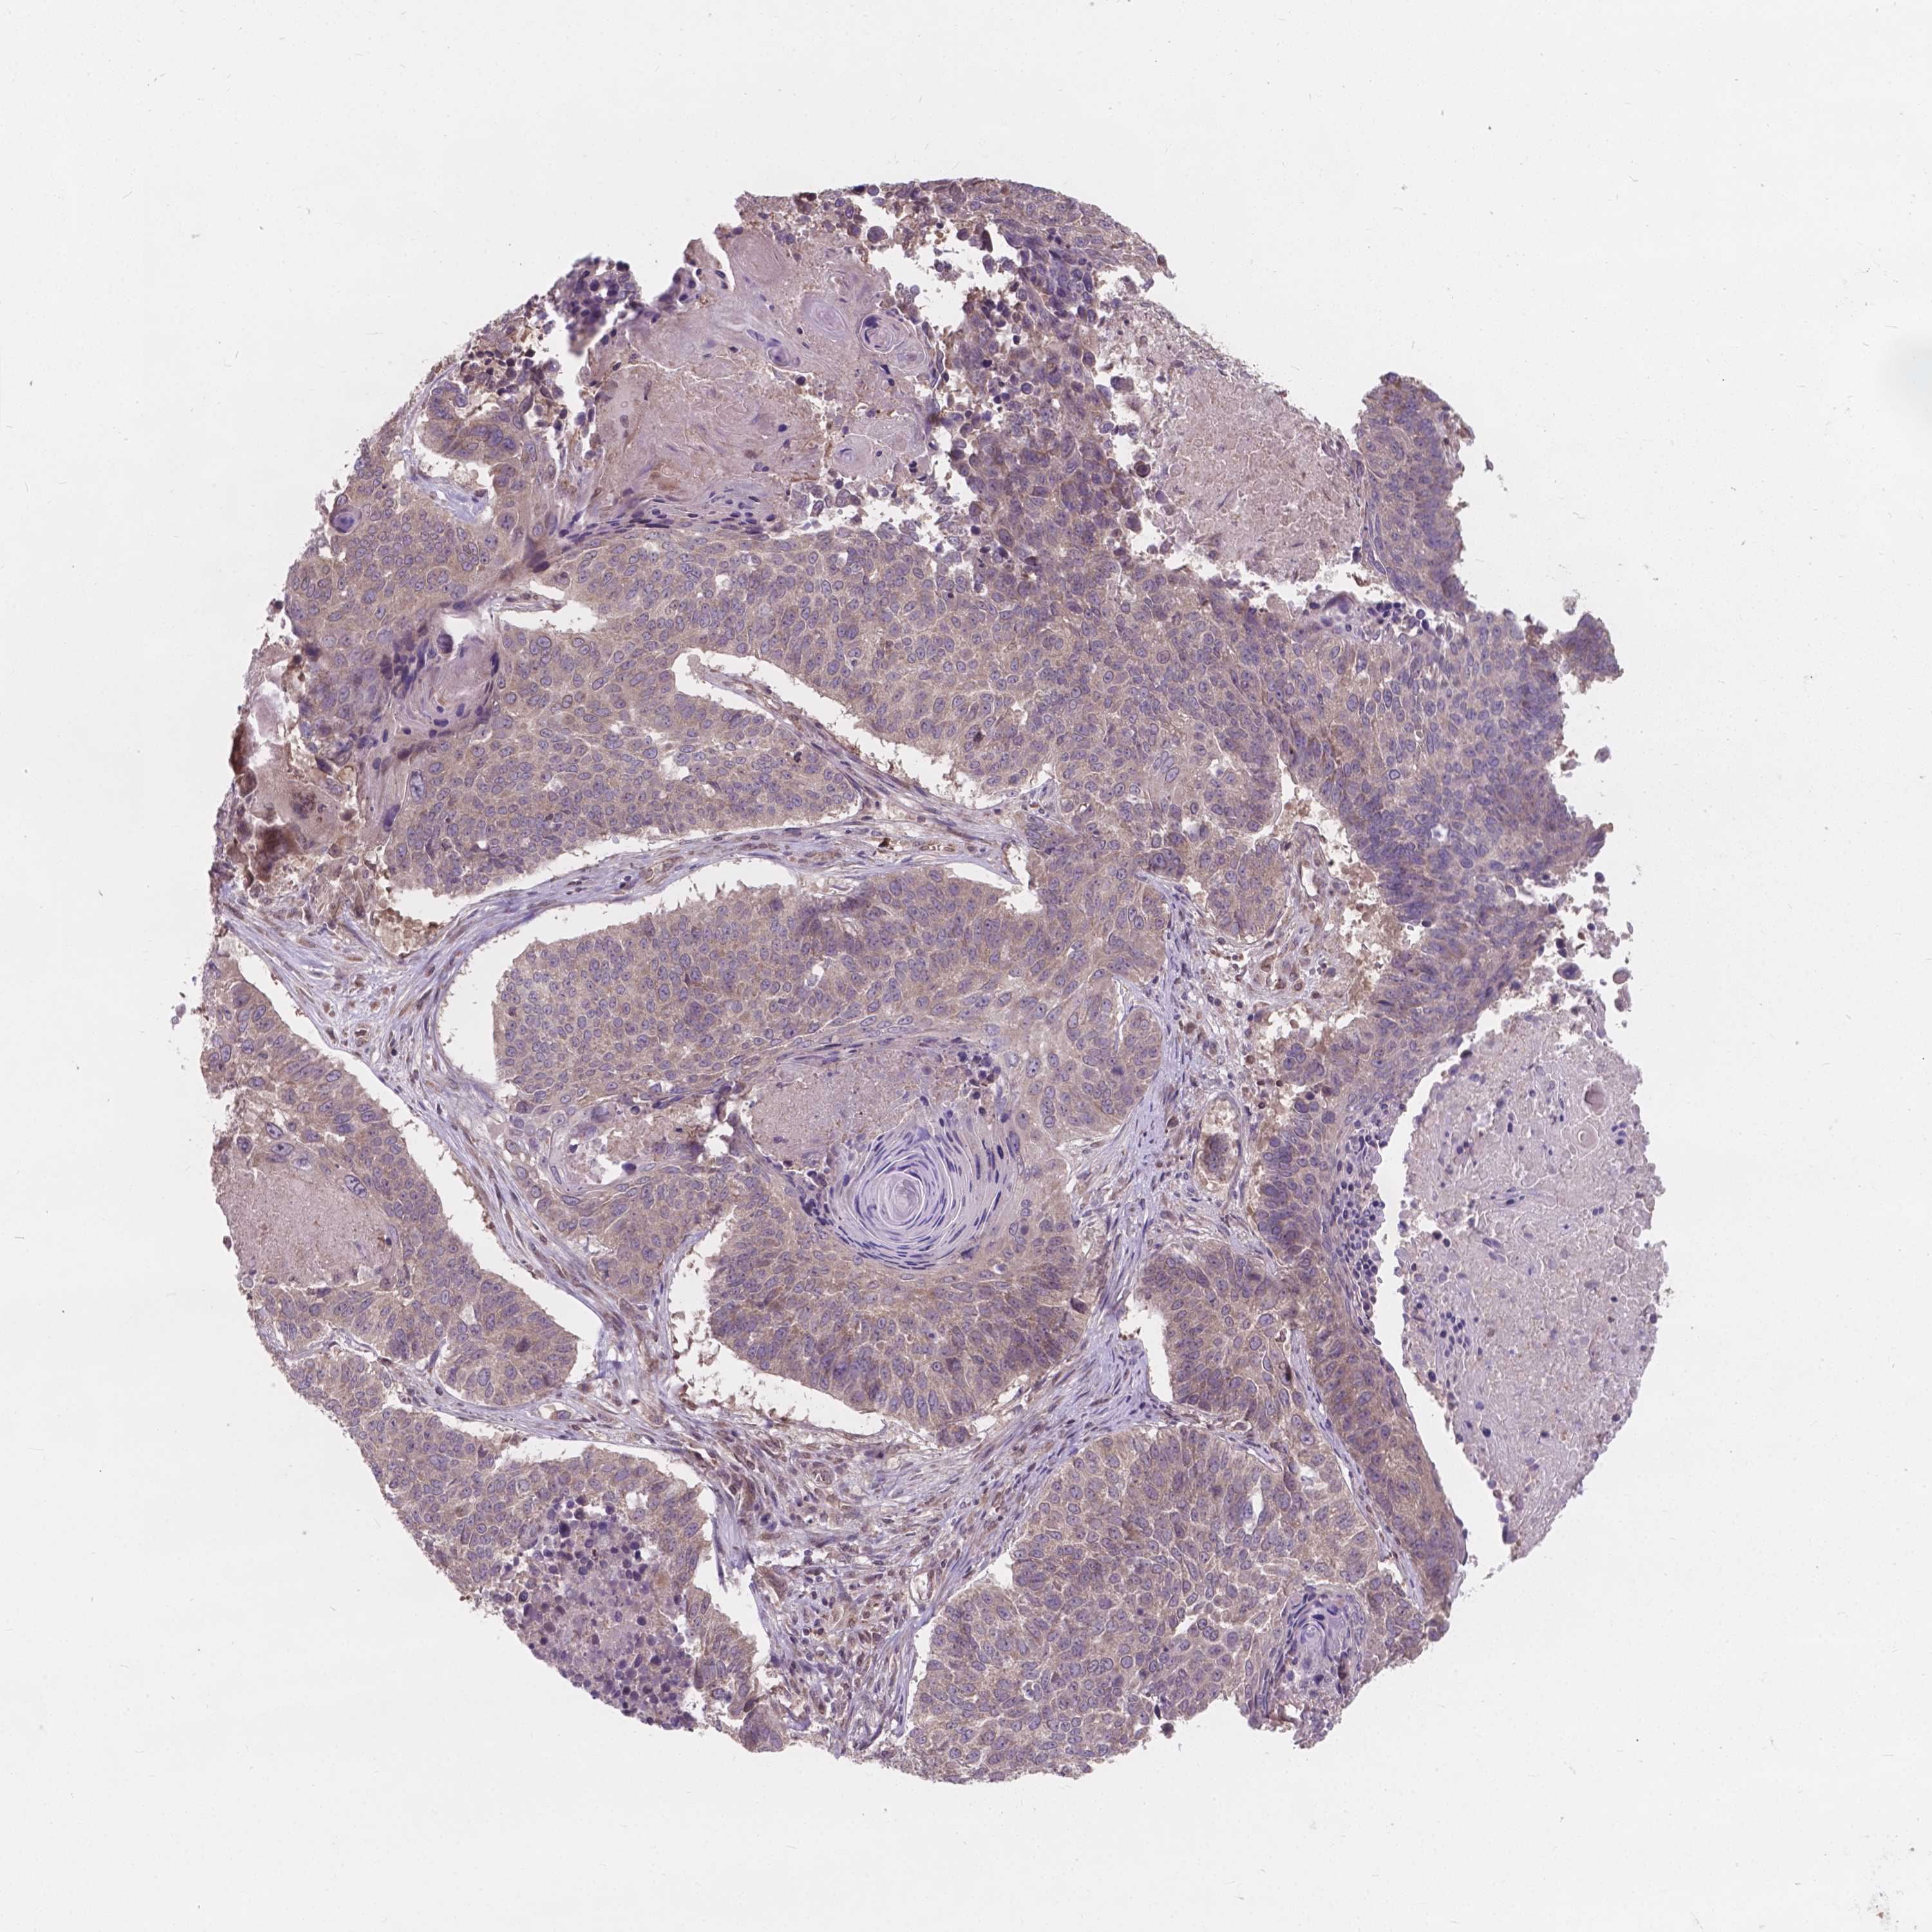

LUNG SQUAMOUS CELL CARCINOMA (TCGA) - Interactive survival scatter ploti

The Survival Scatter plot shows the clinical status (i.e. dead or alive) for all individuals in the patient cohort, based on the same data that underlies the corresponding Kaplan-Meier plots. Patients that are alive at last time for follow-up are shown in blue and patients who have died during the study are shown in red.

The x-axis shows the expression levels (FPKM) of the investigated gene in the tumor tissue at the time of diagnosis. The y-axis shows the follow-up time after diagnosis (years). Both axes are complimented with kernel density curves demonstrating the data density over the axes. The top density plot shows the expression levels (FPKM) distribution among dead (red) and alive patients (blue). The right density plot shows the data density of the survived years of dead patients with high and low expression levels respectively, stratified using the cutoff indicated by the vertical dashed line through the Survival Scatter plot. This cutoff is automatically defined based on the FPKM cutoff that minimizes the p-score. The cutoff can be changed by dragging the vertical line or by entering a cutoff value in the square labeled "Current cut-off".

Under the Survival Scatter plot the p-score landscape (black curve; left axis) is shown together with dead median separation (red curve; right axis). Dead median separation is the difference in median mRNA expression between patients who have died with high and low expression, respectively. It is calculated as follows: median FPKM expression of dead patients with high expression - median FPKM expression of dead patients with low expression. This is intended to aid the user in visually exploring custom cutoffs and the associated p-scores and dead median separation.

Individual patient data is displayed and can be filtered by clicking on one or more of the category buttons on the top of the page. Categories describing expression level and patient information include: high, low, alive, dead, female, male and tumor stages. The scale of the x-axis can be toggled between linear and log-scale by clicking on the "x log" button. Mouse-over function shows TCGA ID, patient information and mRNA expression (FPKM) for each patient.

& Survival analysisi

Kaplan-Meier plots summarize results from analysis of correlation between mRNA expression level and patient survival. Patients were divided based on level of expression into one of the two groups "low" (under cut off) or "high" (over cut off). X-axis shows time for survival (years) and y-axis shows the probability of survival, where 1.0 corresponds to 100 percent.

MRPL33 is not prognostic in Lung Squamous Cell Carcinoma (TCGA)

Best expression cut offi

Based on the FPKM value of each gene, patients were classified into two groups and association between prognosis (survival) and gene expression (FPKM) was examined. The best expression cut-off refers the FPKM value that yields maximal difference with regard to survival between the two groups at the lowest log-rank P-value. Best expression cut-off was selected based on survival analysis .

When clicking on this number, the vertical dashed line indicating cut-off, the interactive survival plot, and the Kaplan-Meier curve will be adjusted to show results based on the best expression cut-off.

: 171.24

P scorei

Log-rank P value for Kaplan-Meier plot showing results from analysis of correlation between mRNA expression level and patient survival.

N/A

Average pTPM 153.9

Number of samples 489